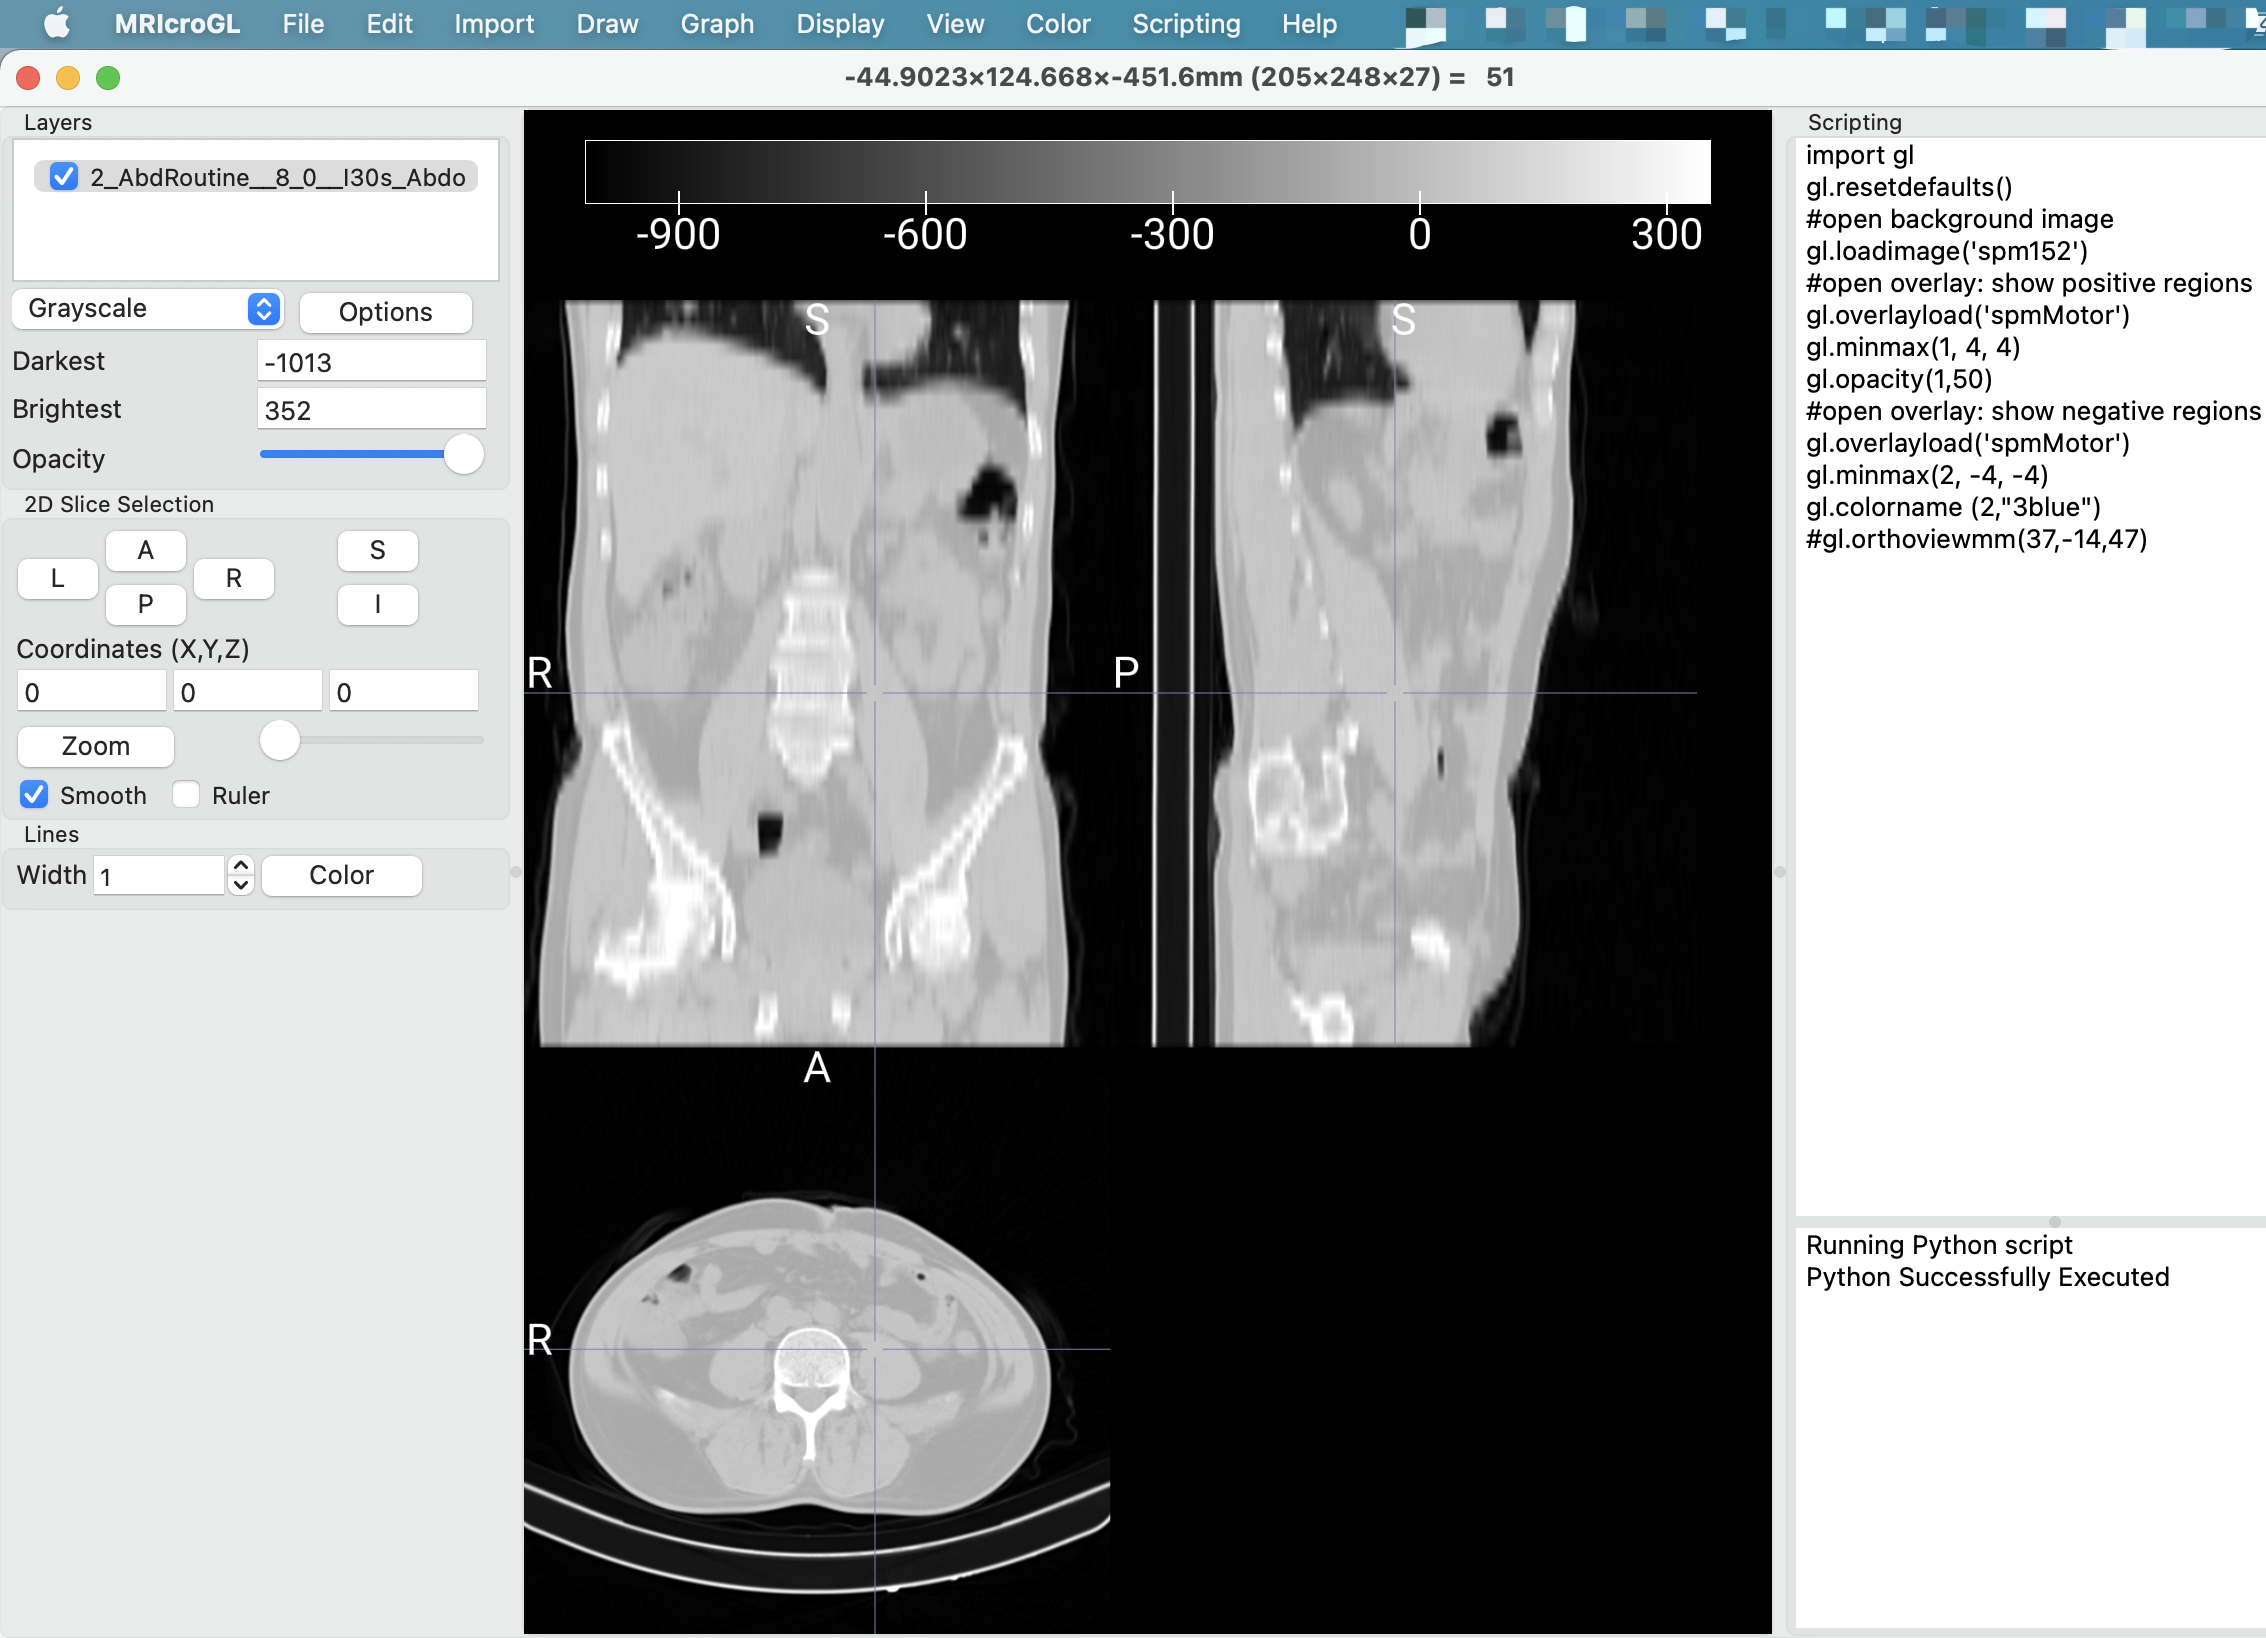

NTRC 团队还开发了 MRICron 软件,这是一款 NIfTI 格式的看图软件,而且它可以方便地调用 dcm2niix 进行图像转换。dcm2niix 的出现使得神经影像学数据的转换和处理更加高效、准确和便捷。

软件打开界面如下图👇

这个界面我还没研究透。还是用 MRICron 比较顺手。